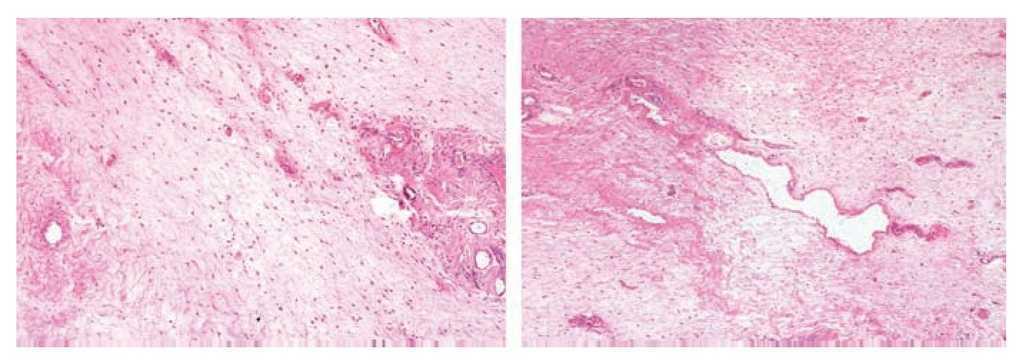

Mujer de 41 años de edad, sin antecedentes, que consultó por historia de dolor pélvico difuso, de baja intensidad, no irradiado, de ocho meses de evolución. Al examen físico se encontró una masa adherida a planos profundos y poco dolorosa a la palpación. Se le realizó una tomografía computadorizada que informó una extensa neoplasia pélvica de características malignas, que se extendía hasta el espacio isquiorectal, con desplazamiento y compresión de la vejiga y el útero, además de escaso líquido alrededor de la lesión (Figura 1). Se realizó una resonancia magnética nuclear que demostró una lesión de 14 x 14 cm, posiblemente de origen lipomatoso con degeneración mixoideangiolipomatosa, con probable infiltración al recto y sigmoides, dilatación pielo-ureteral bilateral por obstrucción del tercio distal de los uréteres (Figuras 2 y 3). Se realizó una colonoscopia que sólo evidenció desplazamiento del sigmoides por compresión extrínseca. Se le realizó una laparotomía exploratoria encontrando una masa pélvica de 15 x 20 cm, la cual se pudo separar de las estructuras adyacentes y resecar en su totalidad. El reporte histopatológico fue de una masa de 15 x 18 cm, con un peso de 260 g, de color amarillo-gris liso y opaco, de aspecto nodular y consistencia blanda. Al corte se encontraron áreas quísticas compatibles con angiomixoma (Figura 4). La paciente presentó una evolución satisfactoria, se le dio egreso. Actualmente se encuentra asintomática y sin datos de recurrencia.

Figura 4. La proliferación neoplásica muestra áreas mixoides hipocelulares alternando con otras de mayor densidad celular con infiltrado inflamatorio mixto y vasos curvilíneos hialinizados.